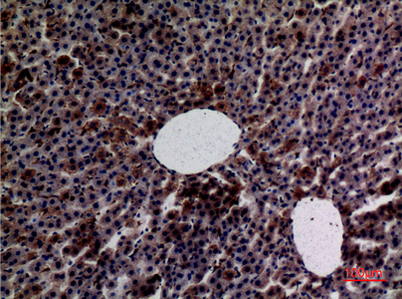

Product name: Amylase rabbit pAb

Dilutions: Western Blot: 1/500 - 1/2000. IHC-p: 1:100-300 ELISA: 1/20000. Not yet tested in other applications.

Immunogen: The antiserum was produced against synthesized peptide derived from the N-terminal region of human AMY1/2. AA range:61-110